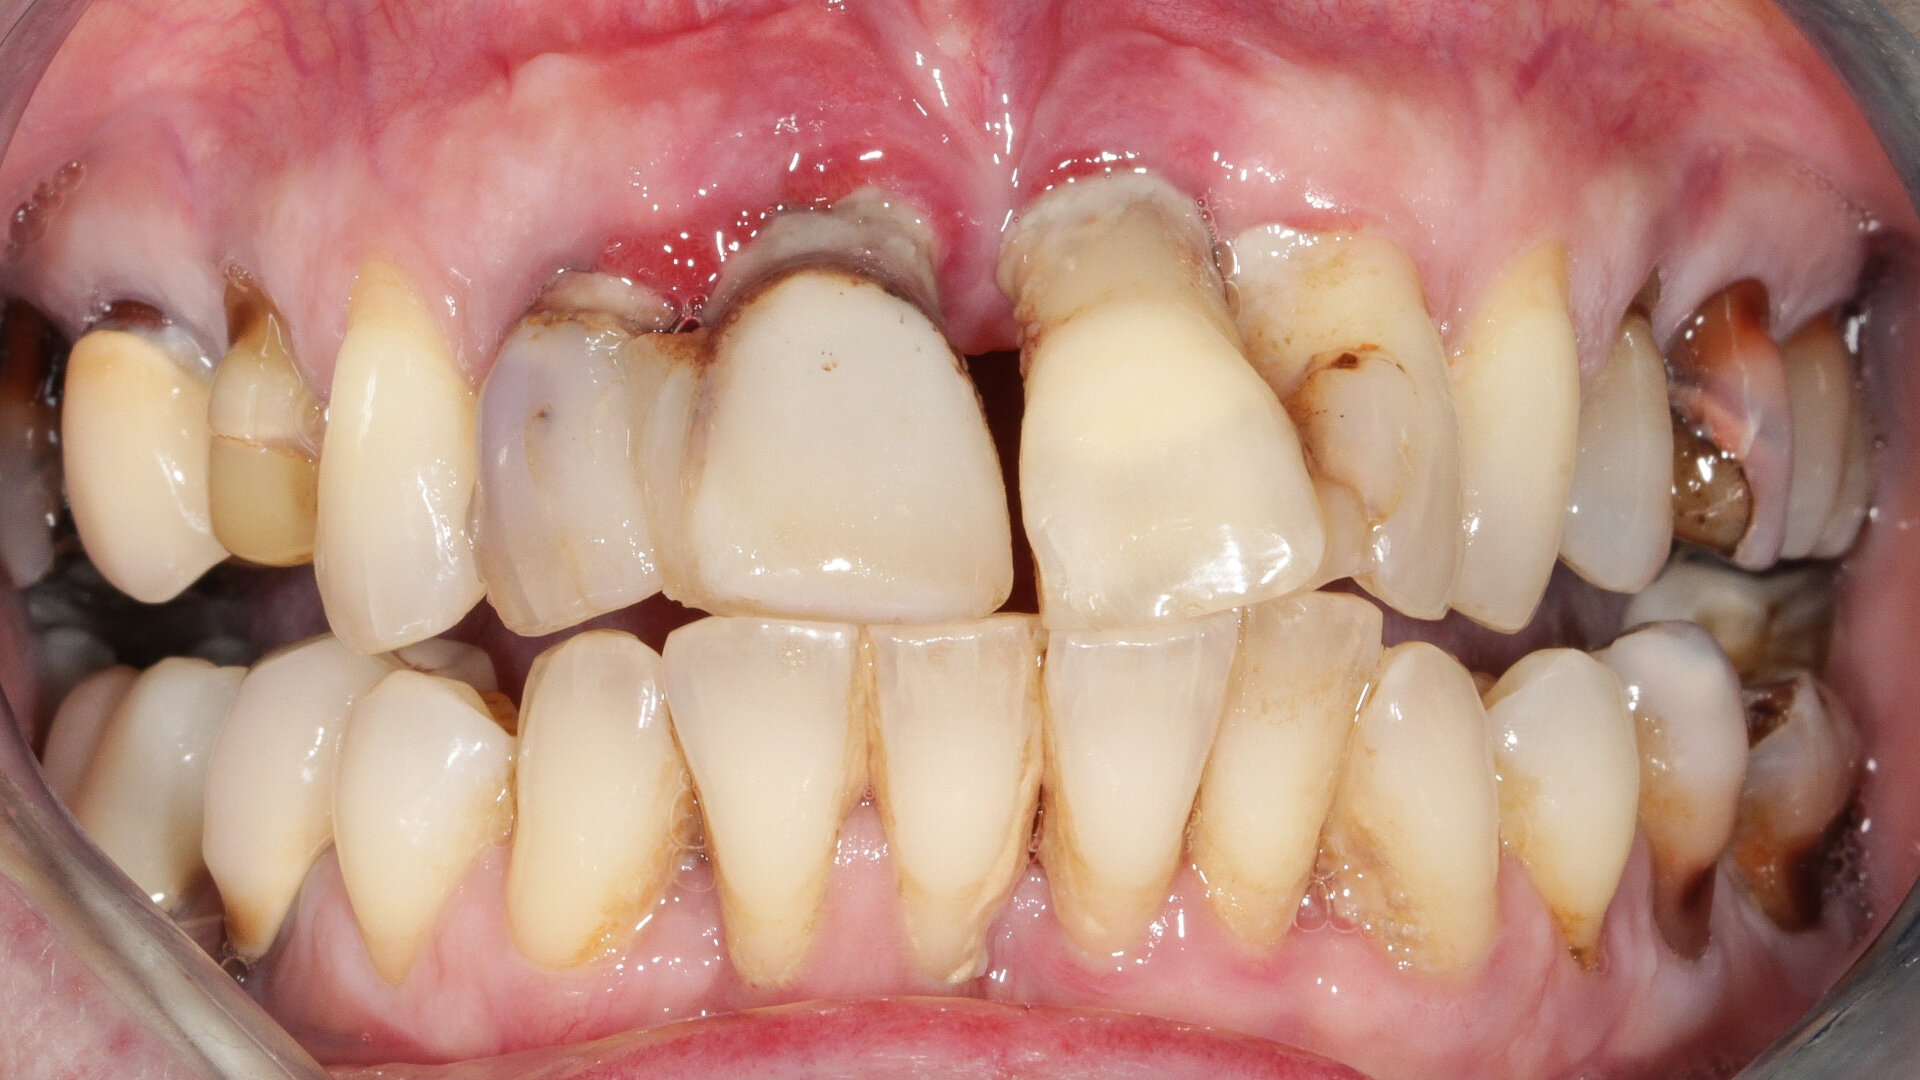

À l’examen, on observe une mobilité des quatre incisives maxillaires, une insuffisance osseuse verticale et horizontale, la présence de plaque, de tartre et d’inflammation gingivale. (Image: Dr Renaud Girieud, France)

À l’examen, on observe une mobilité des quatre incisives maxillaires, une insuffisance osseuse verticale et horizontale, associées notamment au niveau de 11 et 21, la présence de plaque, de tartre et d’inflammation gingivale, surtout au niveau du bloc antérieur maxillaire. On note également la présence d’une dent de sagesse (dent 18) perdue (Figs. 24–26).